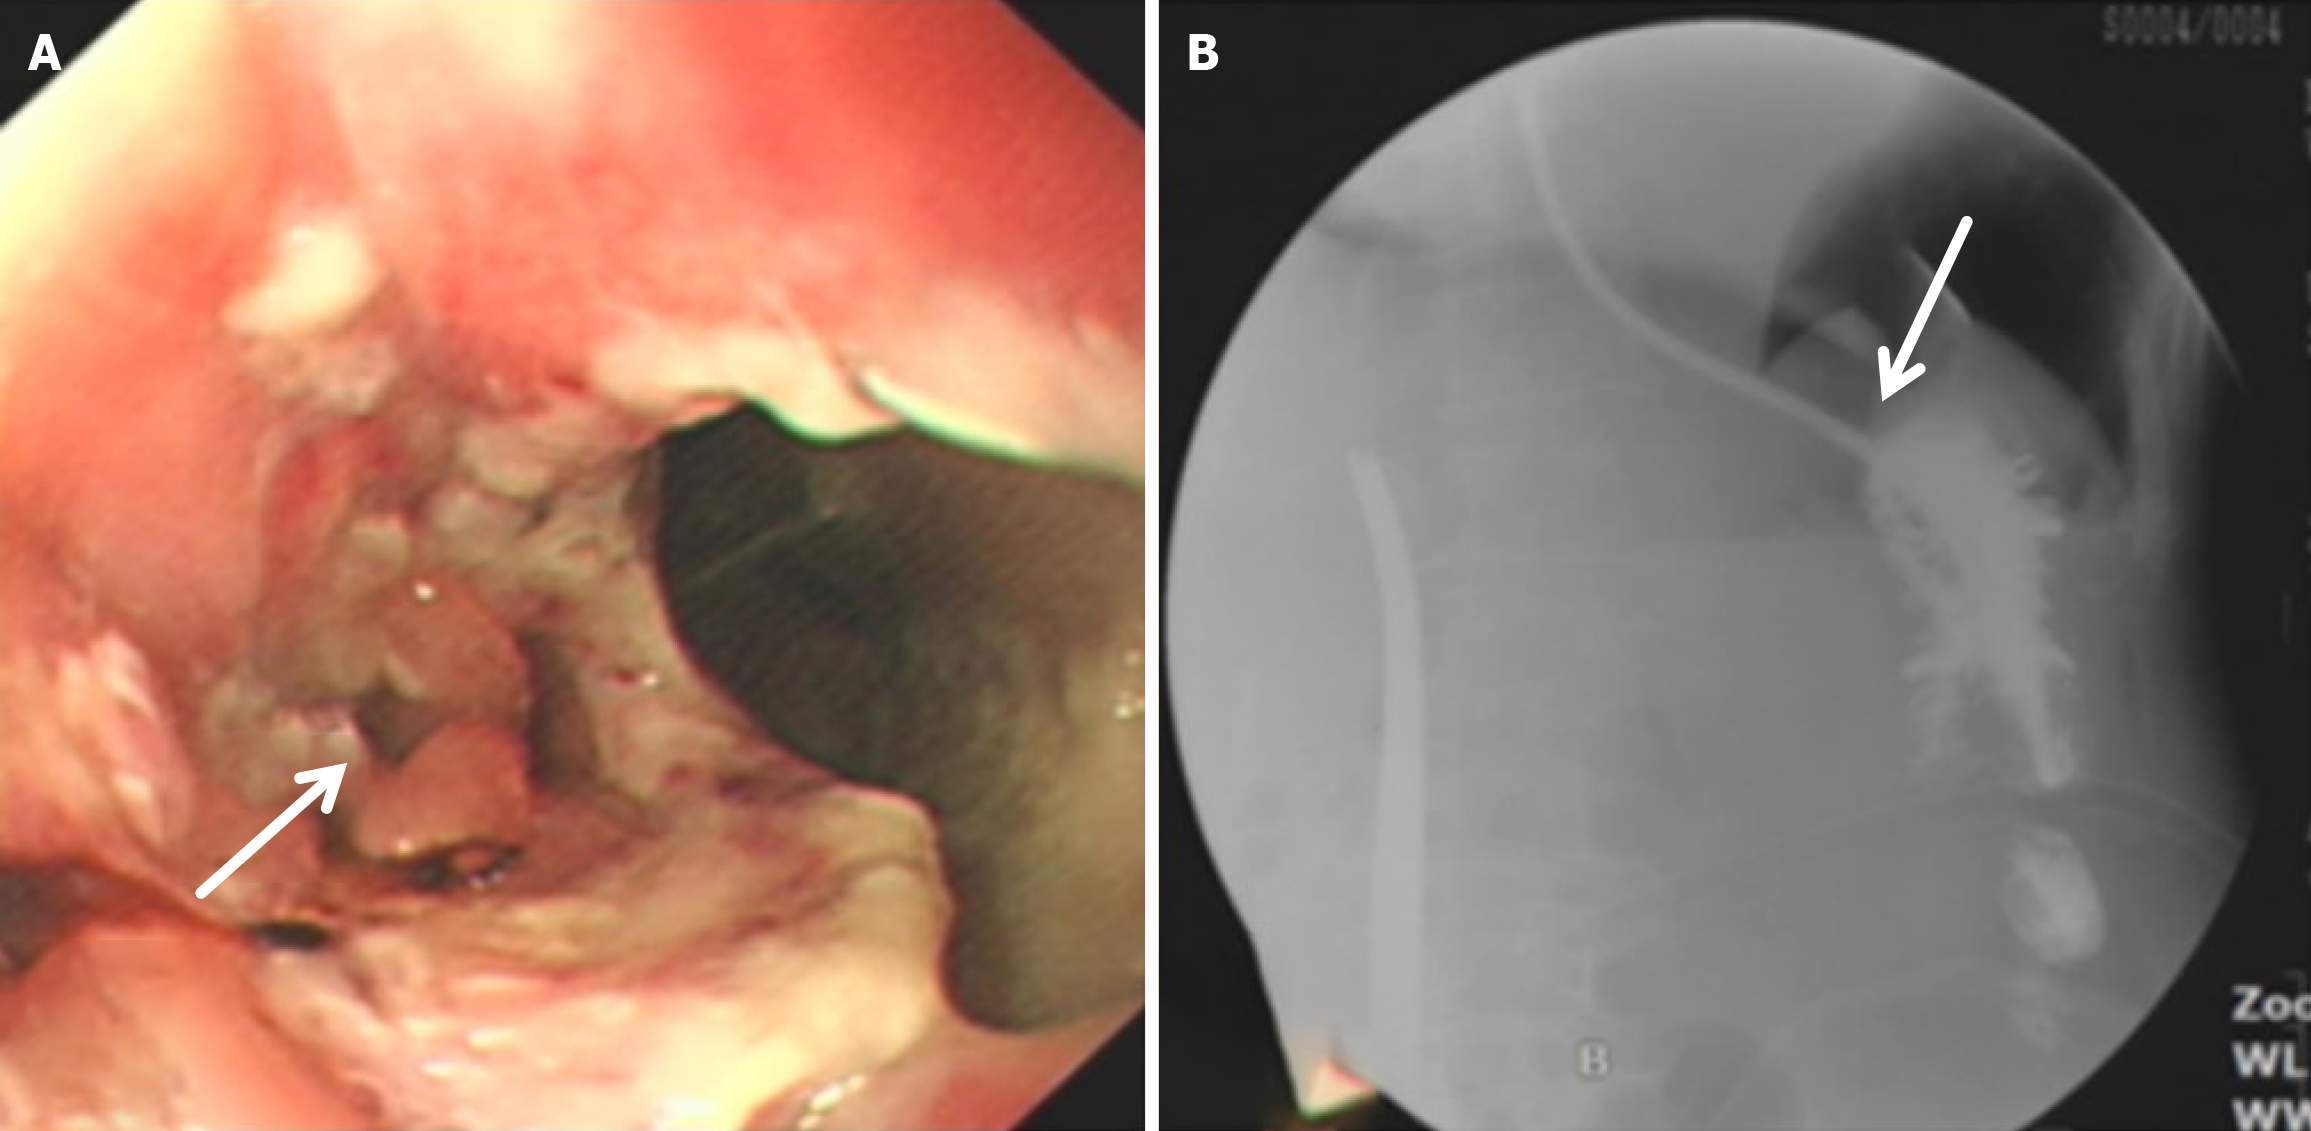

(1) A circular stapler buttress was embedded in the jejunum approximately 65-70 cm distal to the ligament of Treitz. Then the jejunum was fenestrated approximately 15 cm distal to the ligament of Treitz, where a circular stapler was inserted to perform the side - side anastomosis of the proximal jejunum (approximately 15 cm away distal to the ligament of Treitz) and the jejunum (approximately 65-70 cm distal to the ligament of Treitz); (2) The circular stapler buttress was inserted into the lower segment of the esophagus, and then the circular stapler was inserted from the jejunum “fenestration” to perform end - side anastomosis of the jejunum (approximately 25 cm away from the flexor ligament) and the lower esophagus; (3) The jejunum was closed with a linear stapler; and (4) All anastomoses were embedded intermittently with silk thread (Figure 1).

Compared with the modified group, the Orr group had a greater incidence of anastomotic leakage (AL) and short-term complications of anastomotic ischemia, although there was no significant difference between the two groups. Furthermore, Fisher’s exact probability analysis revealed that the incidence of reflux esophagitis, anastomotic ulcers by endoscopic examination, and intestinal obstruction in the Orr group was greater than that in the modified group at the 6-month postoperative follow-up period (P < 0.05) (Tables 3, 4 and 5).

After total gastrectomy, due to the loss of antireflux function of the cardia, the reverse peristaltic wave generated by the pacing cells of the duodenum leads to the reflux of food and bile into the esophagus, resulting in clinical symptoms such as reflux esophagitis and other gastrointestinal duct discomfort[21]. Previous studies have shown that the jejunal storage bag after total gastrectomy can effectively relieve the pressure of food passing through the esophagojejunostomy. When food flows back from the distal output loop, the storage bag has a similar “siphon effect” to play an antireflux role and reduce the incidence of reflux esophagitis[22]. The antireflux effect is positively proportional to the length of the jejunal storage bag; nevertheless, a storage bag that is too long increases the incidence of Roux stasis syndrome, and the ideal length is approximately 5 cm[23]. In our study, storage bags with a length of approximately 5 cm were constructed at the anastomosis of the esophagus and jejunum in both groups. Our results revealed that the incidence of reflux esophagitis in the Orr group was greater than that in the improved group (P < 0.05), which occurred because the jejunal storage bag was constructed after the jejunum and its mesentery were disconnected, and the residual end of the storage bag lacked traction of the mesentery in the Orr group; therefore, the “siphon effect” was weakened. By contrast, the storage bag of patients in the improved group only needed to disconnect the jejunum, and the jejunal mesentery was continuous, resulting in strong negative pressure suction.